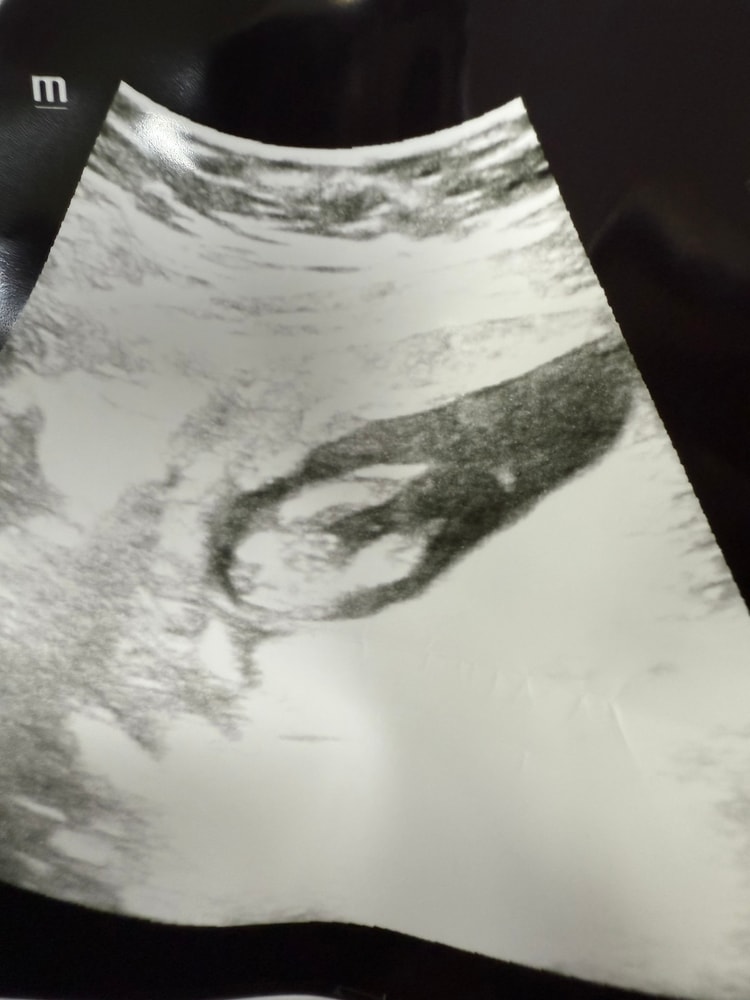

6 недель 1 день

плодное 10мм

Желточный 4,2

Ктр 1,5

6 недель 4 дня

Плодное 12,3

Ктр 1,7

Мерцание есть и в, 6, 1недель и 6,4 недель

Сердцебиение не мерили сказали маленький ещё ктр.